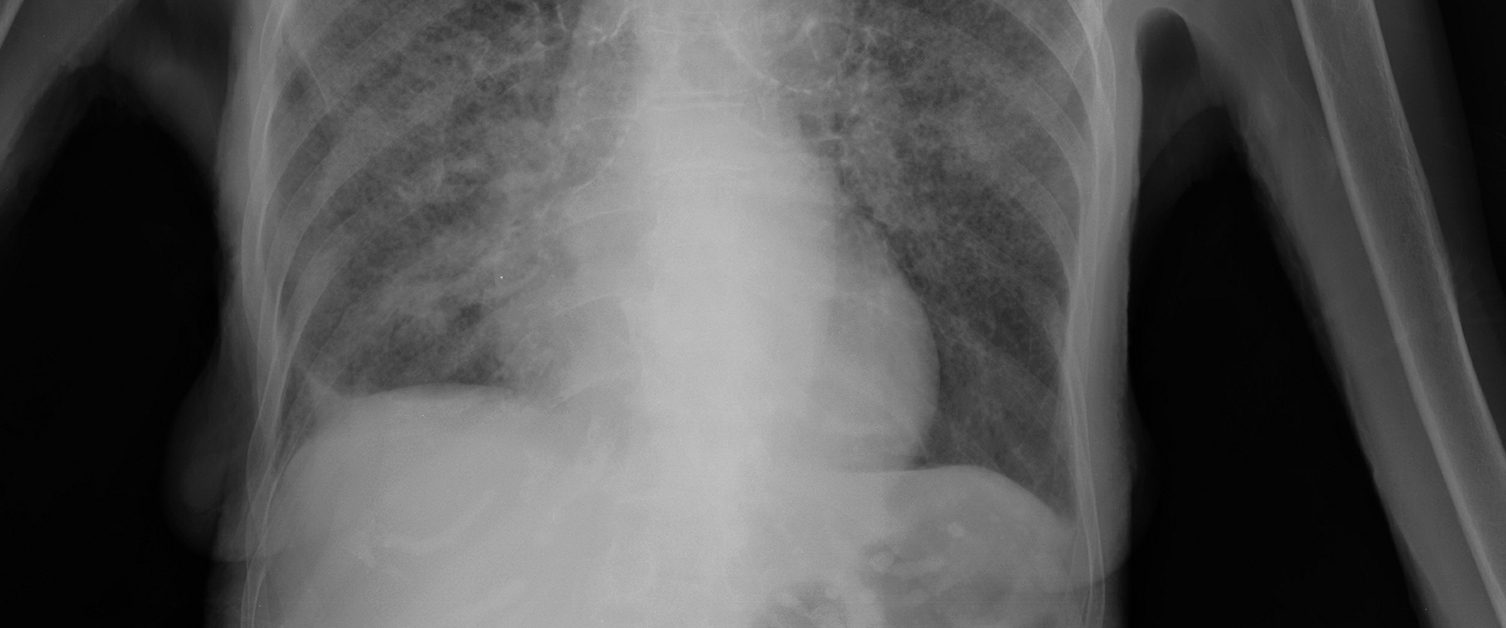

x-ray of lungs with tb

Tuberculosis (TB) is a bacterial infection spread through inhaling tiny droplets from coughs and sneezes from someone infected with Tuberculosis. It mainly affects the lungs but can affect other parts of the body.